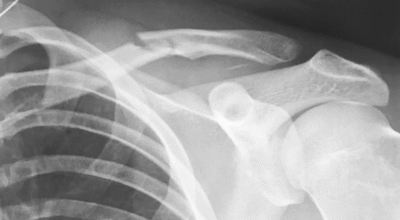

Brooklyn ha sufrido un accidente mientras hacía Snowboard en la nieve que ha termina en rotura.

Pero, como todo deporte, hay veces que uno corre riesgos. El joven se fue a la montaña con unos amigos a disfrutar de un día de snowboard y el día no terminó lo que se puede decir muy bien. Y es que Brooklyn terminó con una clavícula rota. Lo que tienen las redes sociales: todo sale a la luz. ​

Tal y como ha enseñado el propio Brooklyn en su intsagram, ya que hay vídeo incluso de la caída fatídica, un mal golpe ha terminado con el joven ingresado en una clínica ya que una dolorosa rotura le mantendrá alejado de este deporte un tiempo.